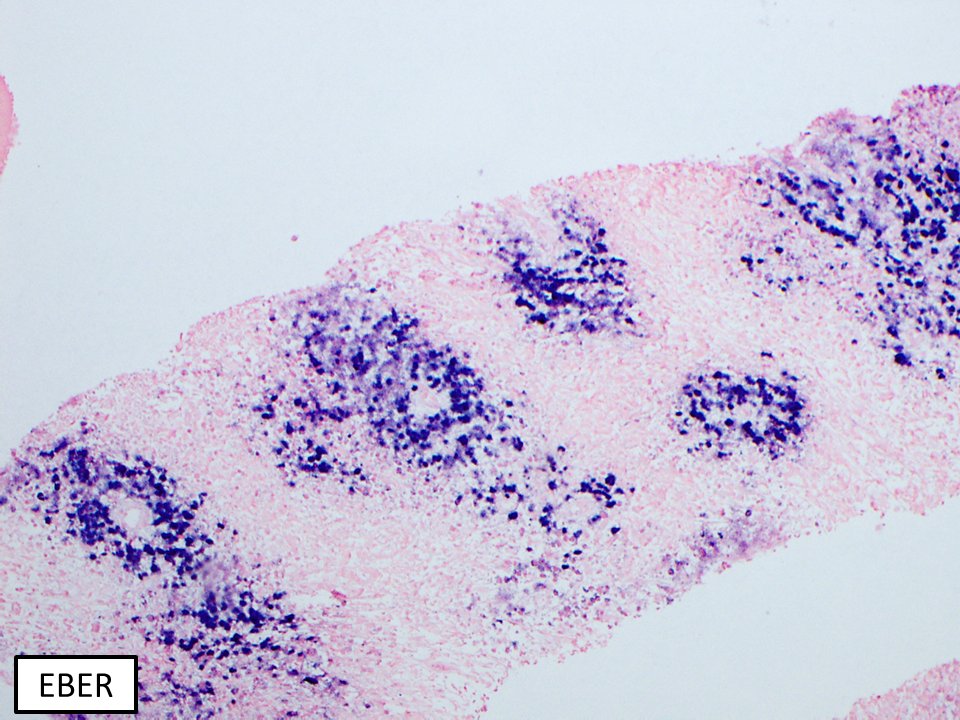

What's your diagnosis of this EBV+ B-cell lymphoma? Adult female, HIV+ with adenopathy. Poor compliance on HAART. WSI + IHCs: http://the.pathology.network/share/f4ffc9dc38c3c5132913f81b67b02a3c …

#hemepath pic.twitter.com/wt99agWd0v